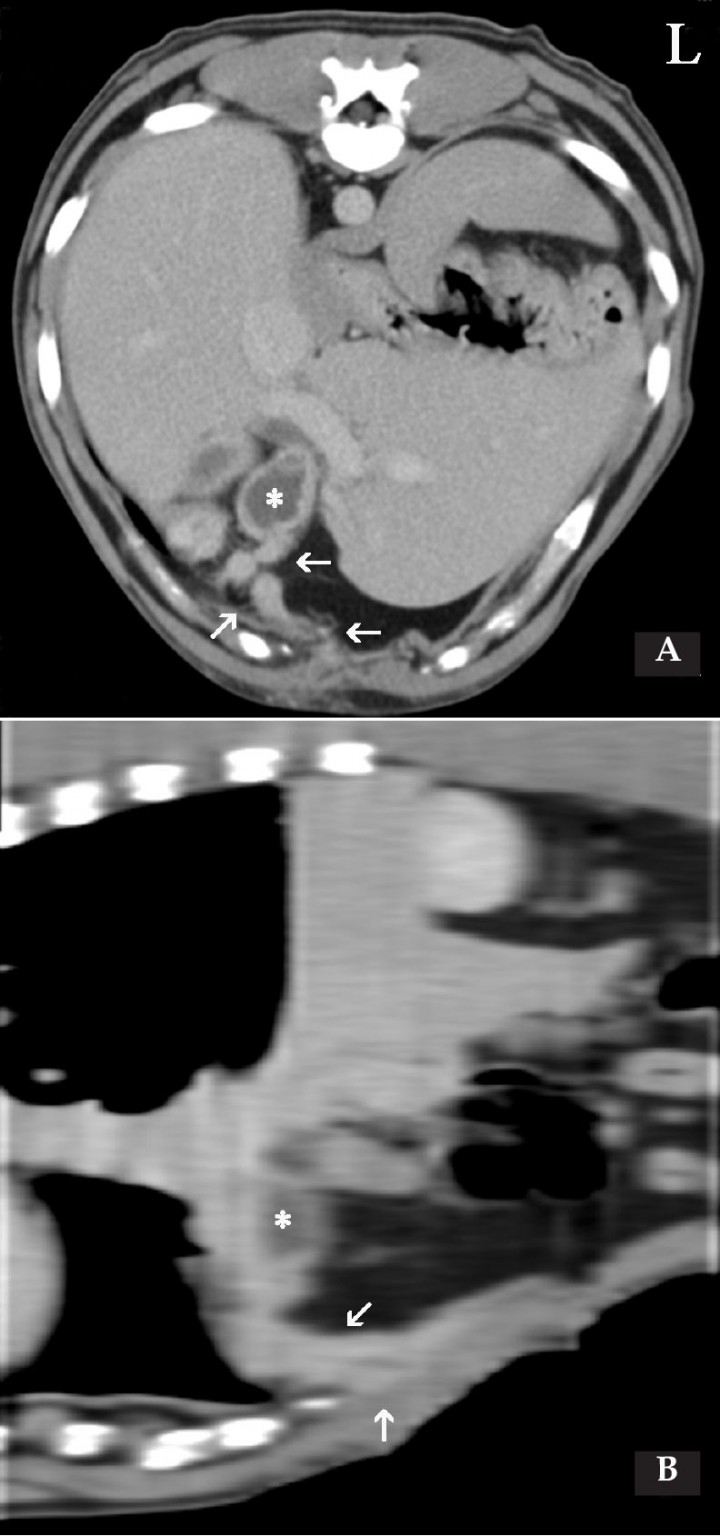

Con el objetivo de localizar el origen de la fístula y poder planificar la cirugía, se realizó una tomografía computarizada (TC) de la cavidad abdominal (Fig. 2) en la que se observó la pared de la vesícula biliar engrosada e irregular y con pequeñas estructuras hiperdensas como contenido. La vesícula biliar se localizaba en posición anómala, en situación ventromedial, y presentaba adherencias a una estructura isodensa respecto a la musculatura abdominal, que se extendía hacia la pared abdominal. Tras la administración del contraste, dicha estructura realzaba en anillo, lo que resultaba compatible con un trayecto fistuloso. La fistulografía en TC reveló una acumulación irregular del contraste en el tejido subcutáneo de la pared abdominal en el área ventrolateral, aunque no se visualizó en la vesícula biliar, el hígado o el tracto biliar.

<p>Caso 1. Imágenes de Tomografía Computarizada (TC) en ventana de tejido blando, post-contraste. (<strong>A</strong>) Plano transversal. (<strong>B</strong>) Plano sagital. Se visualiza un engrosamiento de la pared abdominal; en su interior se observa una estructura tubular y tortuosa con un realce periférico homogéneo (109 UH) con un centro hipoatenuante que se corresponde a un trayecto fistuloso (flechas), el cual se origina caudal a la apófisis xifoides a nivel de la línea alba, y se extiende craneal y dorsal hasta el interior de la cavidad abdominal (flechas) para terminar adyacente a la vesícula biliar (*) que presenta la pared engrosada e irregular. L: Izquierdo.</p>

Caso 1. Imágenes de Tomografía Computarizada (TC) en ventana de tejido blando, post-contraste. (A) Plano transversal. (B) Plano sagital. Se visualiza un engrosamiento de la pared abdominal; en su interior se observa una estructura tubular y tortuosa con un realce periférico homogéneo (109 UH) con un centro hipoatenuante que se corresponde a un trayecto fistuloso (flechas), el cual se origina caudal a la apófisis xifoides a nivel de la línea alba, y se extiende craneal y dorsal hasta el interior de la cavidad abdominal (flechas) para terminar adyacente a la vesícula biliar (*) que presenta la pared engrosada e irregular. L: Izquierdo.